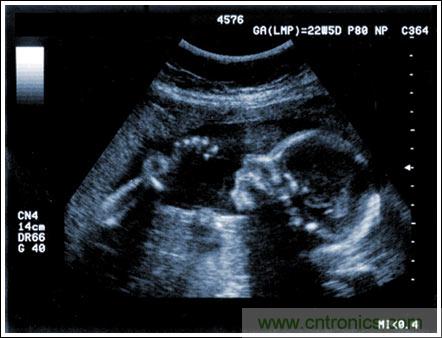

【導讀】該應用筆記介紹了超聲成像係統的設計考慮,討論成像係統的小型化、低(di)成(cheng)本(ben)和(he)便(bian)攜(xie)化(hua)的(de)發(fa)展(zhan)趨(qu)勢(shi),同(tong)時(shi)闡(chan)述(shu)了(le)在(zai)小(xiao)型(xing)係(xi)統(tong)中(zhong)實(shi)現(xian)大(da)型(xing)車(che)載(zai)係(xi)統(tong)所(suo)具(ju)備(bei)的(de)性(xing)能(neng)和(he)診(zhen)斷(duan)能(neng)力(li)的(de)重(zhong)要(yao)條(tiao)件(jian)。文(wen)章(zhang)探(tan)討(tao)了(le)超(chao)聲(sheng)係(xi)統(tong)的(de)子(zi)功(gong)能(neng)以(yi)及(ji)對(dui)電(dian)子(zi)元(yuan)件(jian)的(de)要(yao)求(qiu),重(zhong)點(dian)討(tao)論(lun)了(le)傳感器、高壓複用器、高壓發射機、成像通道接收機、數字波束成形、波束成形數字信號處理及顯示處理等。